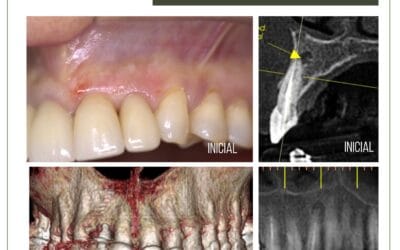

Reabsorção radicular cervical externa

Reabsorção radicular cervical externa. Paciente 30 anos, sexo feminino, com diagnóstico de reabsorção radicular...